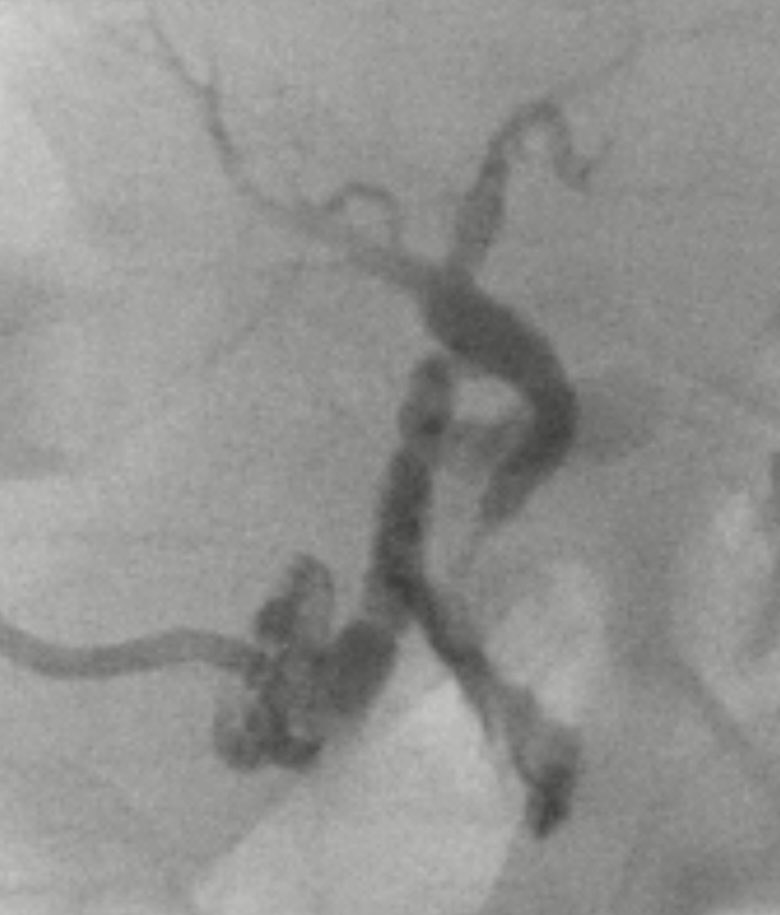

So excited to have matched at @SpectrumHealth @MSUMD in Interventional Radiology! #MatchDay2021 #MSUMDMatch

IR/DR Resident @IRadMSU | MSU CHM alum @MSUMD